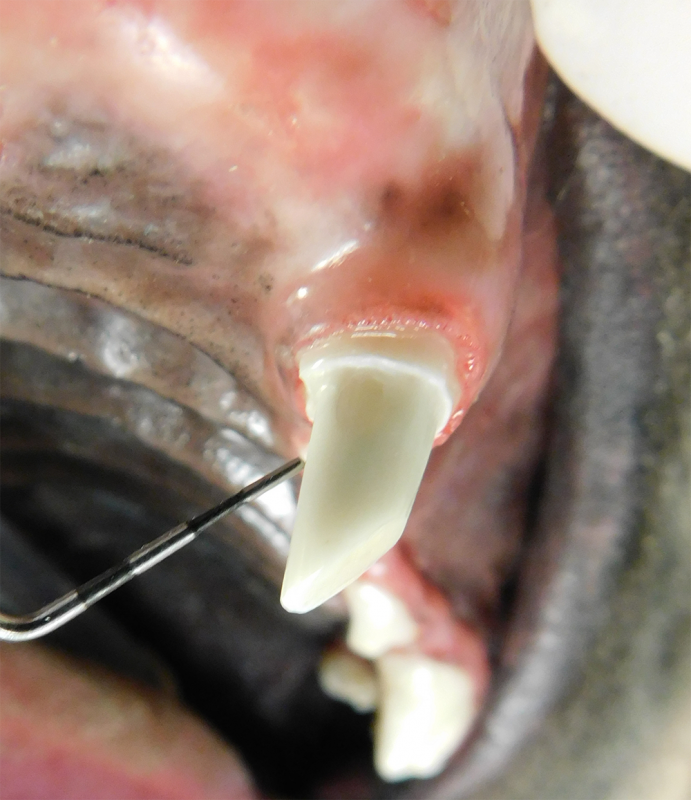

Tooth resorption is a disease process where the body begins to break down the adult tooth. It is widely known to occur in cats but can also occur in dogs. In cats these lesions are thought to be inflammatory, while in dogs they can be more of a replacement resorption process. These lesions can be very painful and should be treated, generally with extraction depending on the type of resorption that is occurring. The disease can be progressive and affect many teeth over several years. It is important to have regular checkups and yearly dental cleanings to monitor for these lesions.